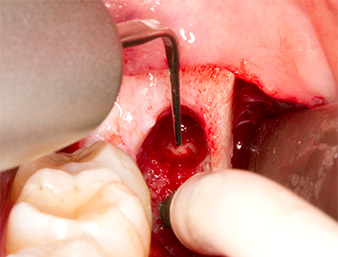

Using an instrument for periodontal debridement (Piezomed P1), the periodontal ligament space of the radix relicta was then widened minimally (Fig. 8).

The same activated instrument was inserted into the root canal and loosened the fragment as a result of its micro-oscillating vibrations (Fig. 9, 10).

Piezomed P1

Fig. 9: The Piezomed P1 instrument is recommended by the manufacturer primarily for periodontal debridement but is also suitable for surgical purposes. Here it is placed in the root canal after minimal widening of the periodontal ligament space.

Fig. 10: Due to its slender shape, the instrument can penetrate the root canal and remove the root remnant by means of micro-oscillation (vibration).

It was then possible to remove the approximately six-millimetre-long root remnant in one piece with the P1 attachment (Fig. 11).